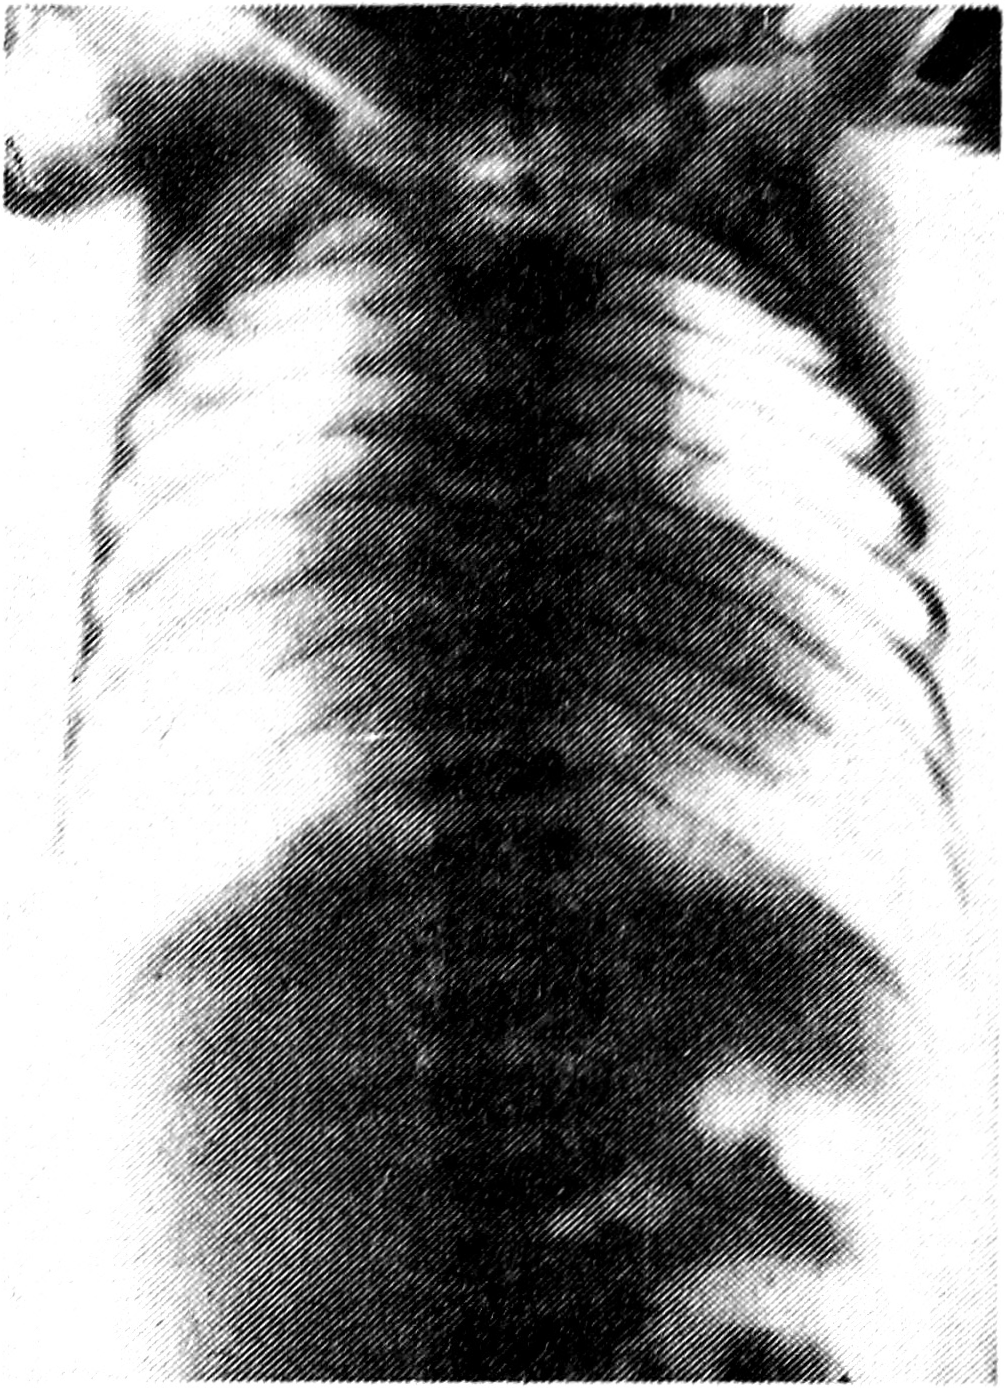

Острую форму болезни Гиршпрунга мы обнаружили у 20 из 23 новорожденных. У 3 детей 7-месячного возраста была установлена хроническая форма болезни. Клинически болезнь Гиршпрунга проявлялась запорами, рвотой с примесью желчи, резким увеличением живота. Рентгенологические исследования выявили у них аганглионарную зону в ректосигмоидальном переходе (у 14), а также в сигмовидной и нисходящем отделе толстой кишки (у 6). Для иллюстрации приводим рентгенограмму брюшной полости новорожденного с аганглиозом (рис. 4).

Рис. 4. На контрастной ирригограмме ребенка месячного возраста определяется участок сужения в ректосигмоидальном переходе с неровными, зубчатыми контурами протяженностью около 3—5 см, обусловленный аганглионарной зоной (оперативное подтверждение).